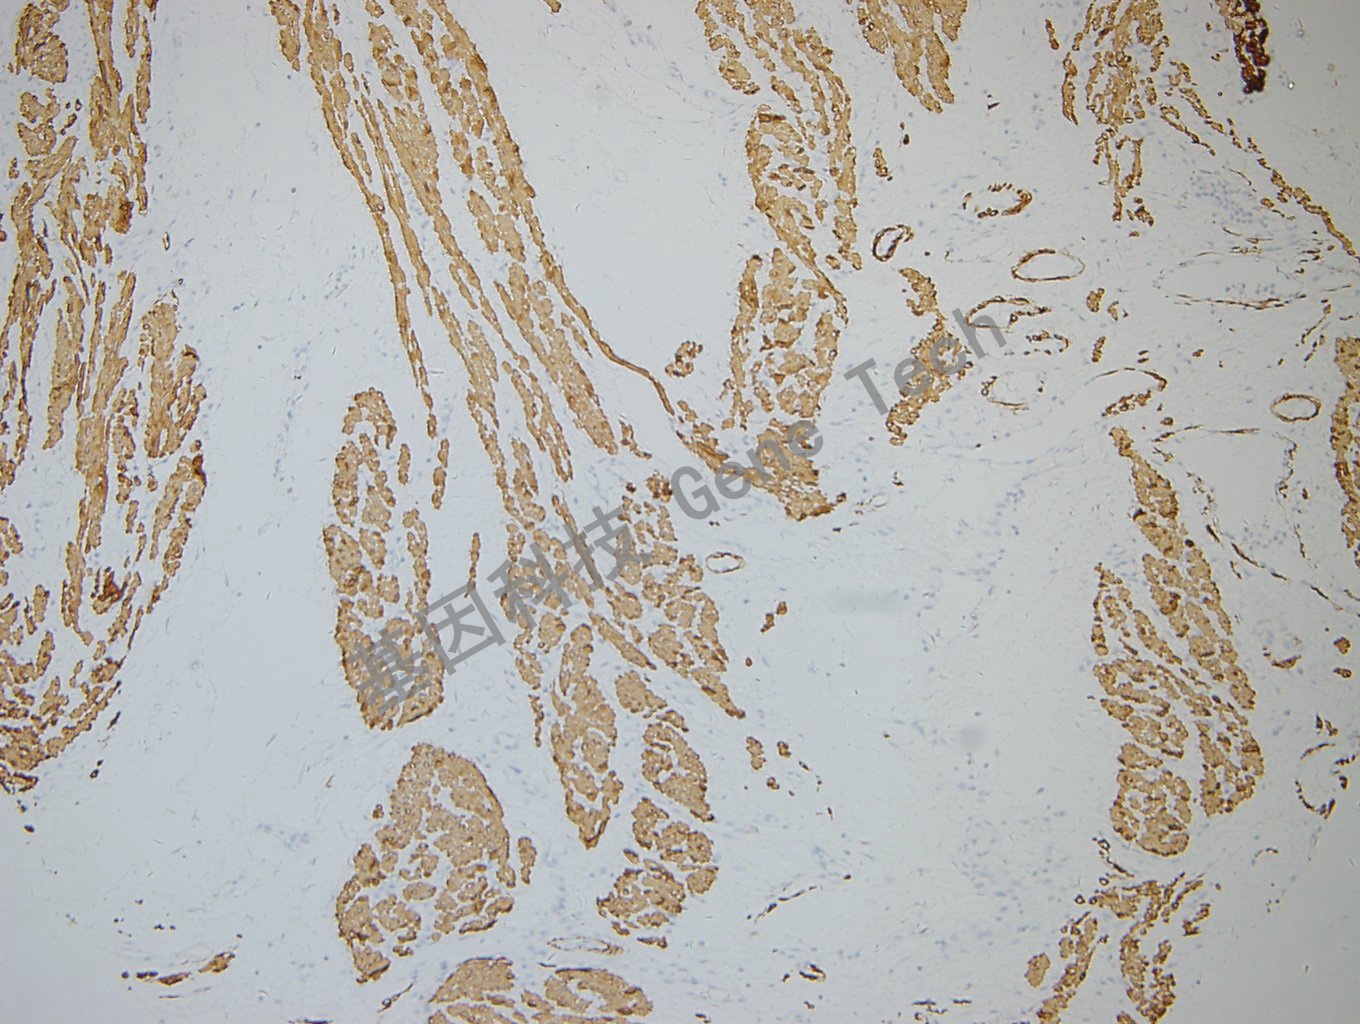

结肠癌石蜡切片,用 Desmin(GT2252)染色,细胞浆阳性,DAB 显色。